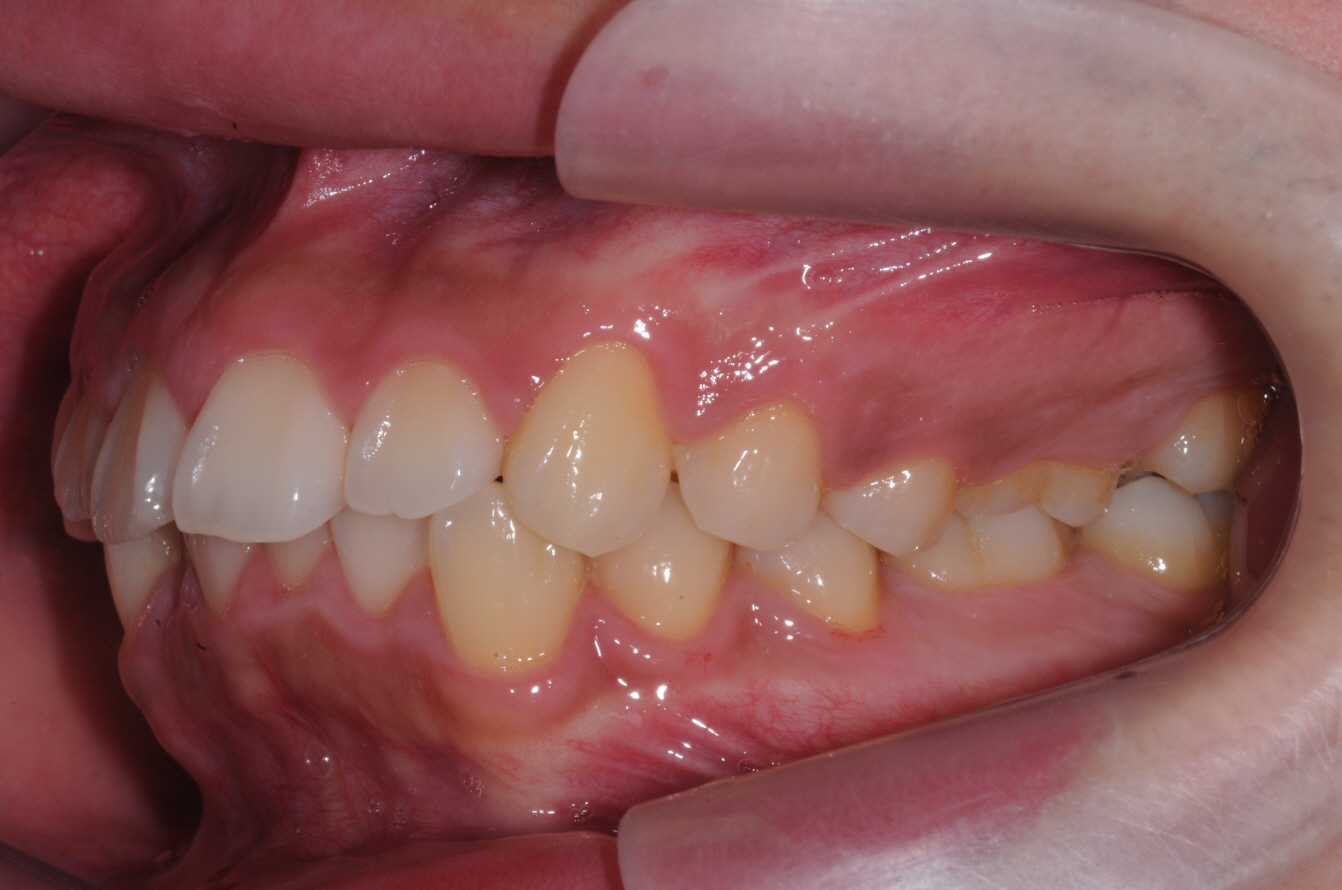

네... 사진 잘 보았습니다. 고민이 많이 되겠군요. 님의 상태는 일반적인 돌출입 부정교합이라고 판단이 됩니다. 그리 어려운 요소도 없구요. 일반적인 브라켓 교정치료로 진행하여도 1년반에서 2년 사이정도에서 교정이 이뤄지리라 예상이 됩니다. 님이 문의하신 교정법들은 치아의 이동을 좀더 빠르게 하는 조치들 인데요. 대략 6개월정도의 단축 효과정도 있으리라 생각이 됩니다. 즉, 1년 남짓정도는 걸리게 되지요. 1번과 3번의 치료방법은 수술의 심적인 부담이 많은 편이랍니다. 2번의 치료는 돌출된 입의 선행적인 치료가 장점이고 치료기간의 메리트는 그리 없지요. 저의 경우는 킬본 교정이라는 장치를 사용하여 2번의 방식데로 치료를 하는 경우가 많이 있는데 주 목적은 치료기간의 단축에 있는 것이 아니라 잇몸돌출의 해소와 앞서 언급한 돌출의 선행적인 해소에 있답니다. 4번의 방법은 님이 진동기를 일정시간 물고 있는 것인데 저는 사용을 하지 않아 뭐라 말씀을 드리기가 그렇습니다. 어쨋든 1번부터 4번까지의 치료는 특별한 부작용이 있는 치료들은 아니랍니다. 님이 언급한 교정치료 중의 애로사항인 심미적인 부분은 장치의 위치를 안으로하는 방법등을 고려해 볼 수 있구요. 발음은 교정치료 후 3개월 정도 되면 대부분 적응을 하는 것 같습니다. 참고가 되셨는지 모르겠네요...^^